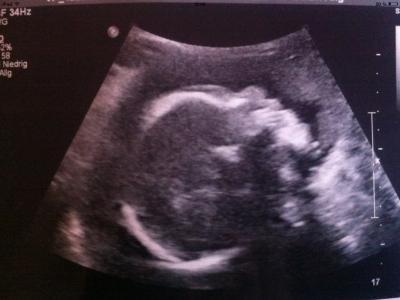

Hey Mädels :) Also erstmal alles gut, is nach wie vor n junge ;) wiegt ca 1111gr und ist ca 37cm groß.. Soweit alles unauffällig und perfekt :) Und an Bibi und Spreemädchen: Hatte die 2.FD wegen schwierigen schallbedinungen. Vorderwandplazenta und noch durch die Gewichtszunahme vom letzten Wurm ;) mir Solls recht sein, mehr Baby TV für mich ;) der kurze war heut mit dabei und hat sich zum Glück auch benommen :) Bildchen hab ich auch wieder welche bekommen.. Diesmal 2 und leider kein 3D. Den hatten wir letztes mal, aber der war nicht so gut.. Hier noch das schönere von beiden Bildern, wie ihr sehen könnt krümelkopf im Profil ;) Kussi

Bild zu Huhu bis wieder da :) und @bibi&spreemädchen - Forum für April - Mamis

Oh wie schön... na dann können wir ja beruhigt sein. Wirklich n tolles Bild...finde es immer wieder Wahnsinn wie gut mM heutzutage alles sehen kann. Und die kleine stupsnase ist echt cool. Gratuliere dir zu diesem kl. Wunder